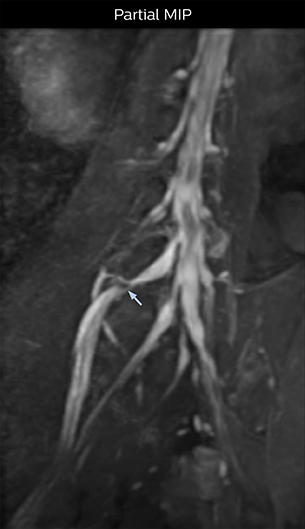

“In such case, we would then browse through axial T2-weighted MR images slice by slice and mentally reconstruct the actual situation based on both radiculography and MRI. Fortunately, NerveVIEW can now very well show nerve courses and presence of nerve compression or edema in one single image series.” “We have often seen NerveVIEW directly depict details of the nerve compression that were not observed by radiculography. Therefore, we think that with NerveVIEW we can reduce the number of invasive examinations, especially for some patients with lumbar plexus symptoms.”

The key concept in MR neurography, Dr. Yabuki stresses, is the ability to directly visualize spinal nerves, versus inferring the presence of pathology indirectly. “Before NerveVIEW, we estimated compression of the nerve by looking for the presence or absence of fat signal on other MR images,” he says.

“For example, in sagittal images, when the presence of fat is observed in the intervertebral foramen, it suggests that there is a margin around the nerve. Similarly, the absence of fat indicates that the nerve is being compressed. So, we used to deduce nerve compression indirectly. With NerveVIEW, however, we can observe the condition of the nerves directly, regardless of the presence or absence of fat. We always prefer such direct observation of anatomy over having to make an inference about it.”

“Recently, the two surgical methods extreme and oblique lateral interbody fusion (XLIF and OLIF) have become mainstream for minimally invasive treatment of lumbar spinal canal stenosis and intervertebral foramen stenosis. With these surgical techniques, the spine is approached from the flank, and prior knowledge of the exact anatomy of the lumbosacral plexus would be extremely helpful. To that end, high slice resolution (less than 1 mm acquisition) that enables sharper sagittal MPR images will be needed.”

“For both brachial and lumbar plexus, we are currently using a 230 mm FOV and voxels of about 1 x 1 x 2 mm acquired (1 x 1 x 1 mm reconstructed). This provides us a good representation of the nerves, even though this FOV is relatively small. Regarding the inplane resolution, we hope to be able to bring that down to 0.7 mm, similar to our typical 2D multislice T2W images,” says Tanji.